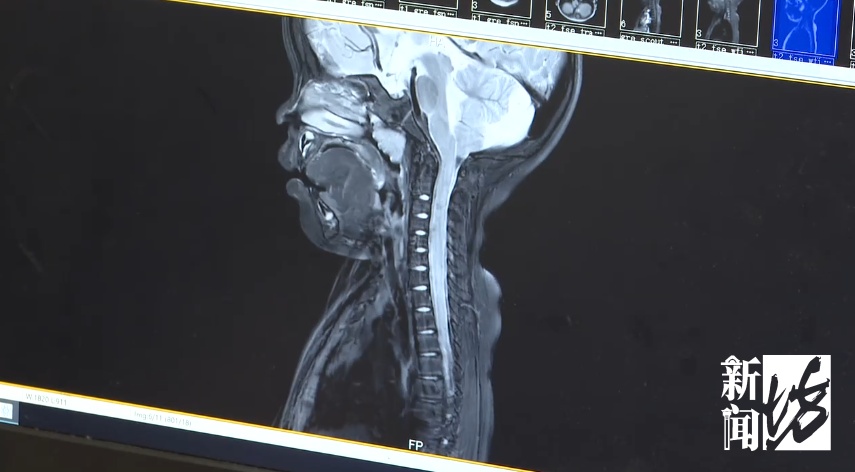

专家介绍,对于此类基因突变型的罕见骨骼发育障碍疾病,生长激素或普通药物几乎无效。但如果不干预,彤彤今后可能会出现睡眠呼吸暂停、脊髓压迫等严重并发症,甚至出现多器官功能障碍。